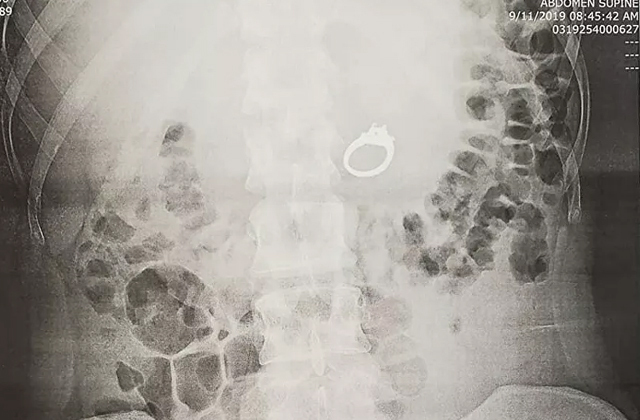

Пост, опубликованный американкой Дженной Эванс в Facebook в 2019 году, быстро стал вирусным. Она поведала историю, которая приключилась с ней как-то ночью. В приснившемся кошмаре жених девушки попросил ее спрятать обручальное кольцо от неких «плохих парней». И предложил проглотить. Дженна так и сделала. А проснувшись, обнаружила, что кольца на пальце нет и проглотила она его не во сне, а наяву. Посмеявшись над случившимся, американка обратилась в службу спасения. Рентген показал, что кольцо действительно находится в желудке. Гастроэнтеролог решил не дожидаться, пока оно выйдет самостоятельно, а извлечь. Женщине провели эндоскопию верхних отделов пищеварительного тракта, в ходе которой достали инородный предмет и на всякий случай отдали жениху. Американка получила его лишь на следующий день, пообещав больше не глотать. Так что свадьба все-таки состоялась.